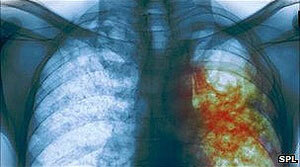

Beýik Britaniýada öýsüz-öwzarsyz adamlaryň

inçekesele ýolugyp-ýolukmandygyny anyklamak

üçin göçme rentgen-otaglaryndan peýdalanýarlar.

Bütindünýä saglygy goraýyş guramasynyň (BSSG) habar bermegine görä, Orsýet, Ukraina we Azerbeýjan Günorta Ýewropanyň ýurtlary bilen bir hatarda rezistent inçekeseliniň (inçekeseliň derman serişdeleri bilen bejerip bolmaýan görnüşi) giňden ýaýran ýurtlarynyň hasabyna girýändir.

Günbatar Ýewropada bu babatda iň ýaramaz ýagdaýa sezewar bolan paýtagtlaryň biri-de Londondyr.

Ýewropada her ýyl köpsanly dermanlara durnukly inçekesele  (KDD-IK) we has agyr ýagdaýlarda — giň gerimli täsiri bolan dermanlara durnukly inçekesele  (GGTD-IK) 81 müňden gowrak adam ýolugýandyr. BSSG bellemegine görä, köp ýurtlarda şeýle inçekesele uçran adamlar ýüze çykarylman galýar.